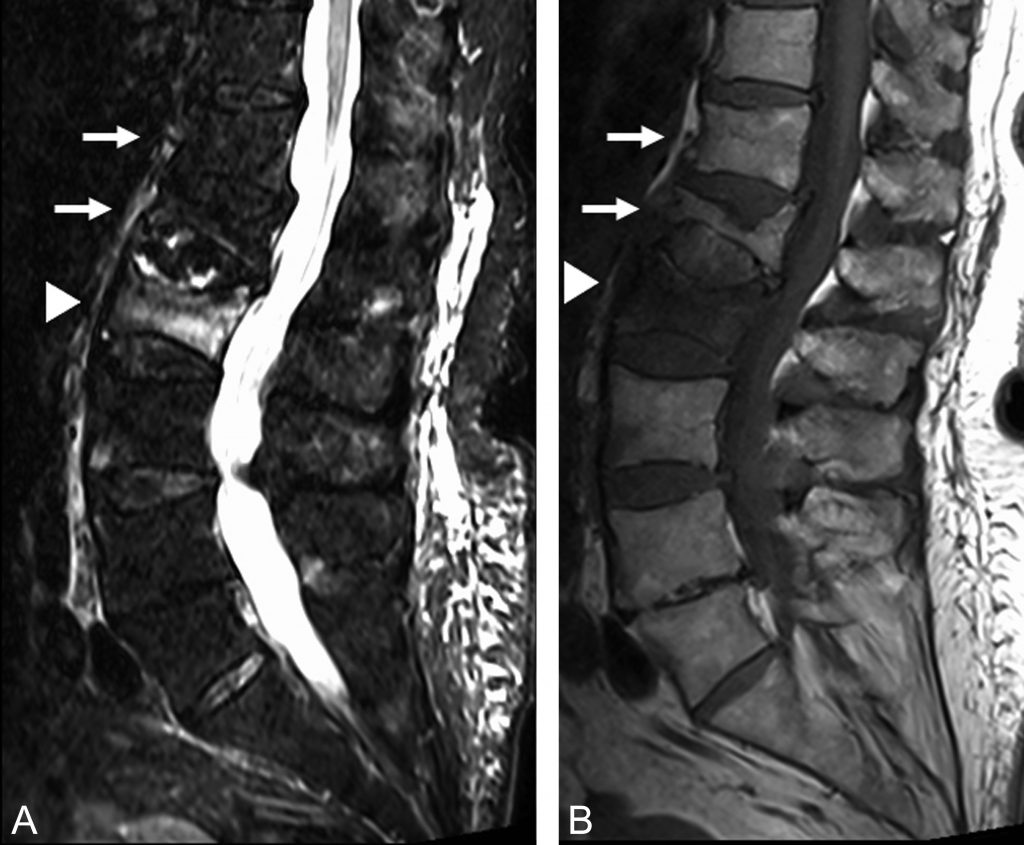

Les principaux critères en IRM en faveur d’un tassement ostéoporotique récent sont (figure 83.2) :

- la présence d’un œdème du corps vetébral (hyposignal T1, hypersignal T2 avec homogénéisation du signal sur les séquences T1 avec injection de gadolinium), qui est évocateur du caractère récent d’une fracture. Ces anomalies de signal sont le plus souvent en bande sous le plateau fracturé ;

- un recul du coin postéro-supérieur ou inférieur ;

- une infiltration paravertébrale ou épidurale absente ou discrète ;

- l’absence d’atteinte de l’arc postérieur ;

- l’absence de masse dans les parties molles paravertébrales ;

- la présence d’autres fractures vertébrales anciennes (perte de hauteur du corps vertébral avec un signal normal).

Une fracture très récente peut se présenter sans perte de hauteur, avec seulement un œdème visible en IRM, qui est donc plus sensible que la radiographie.

Fig. 83.2 IRM du rachis lombaire en STIR (A) et T1 (B) dans un plan sagittal.

L’IRM met en évidence deux fractures porotiques anciennes des vertèbres T12 et L1 (flèches) et une fracture vertébrale récente de L2 (tête de flèche), comme le montre un signal œdémateux du corps vertébral en hyposignal T1 et en hypersignal STIR.

Source : CERF, CNEBMN, 2022.